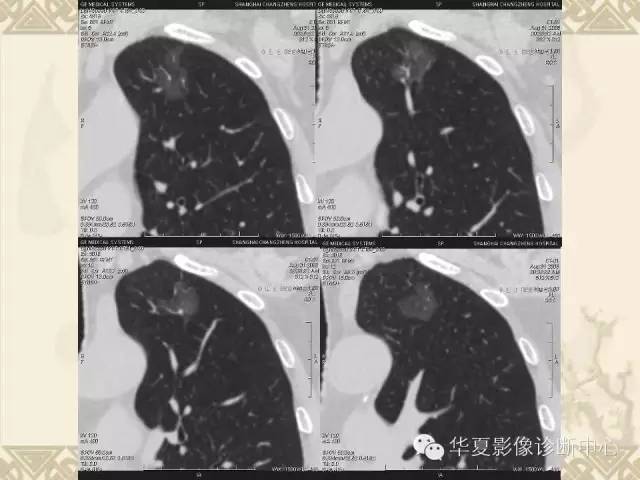

肺内磨玻璃样结节的影像诊断与处理对策